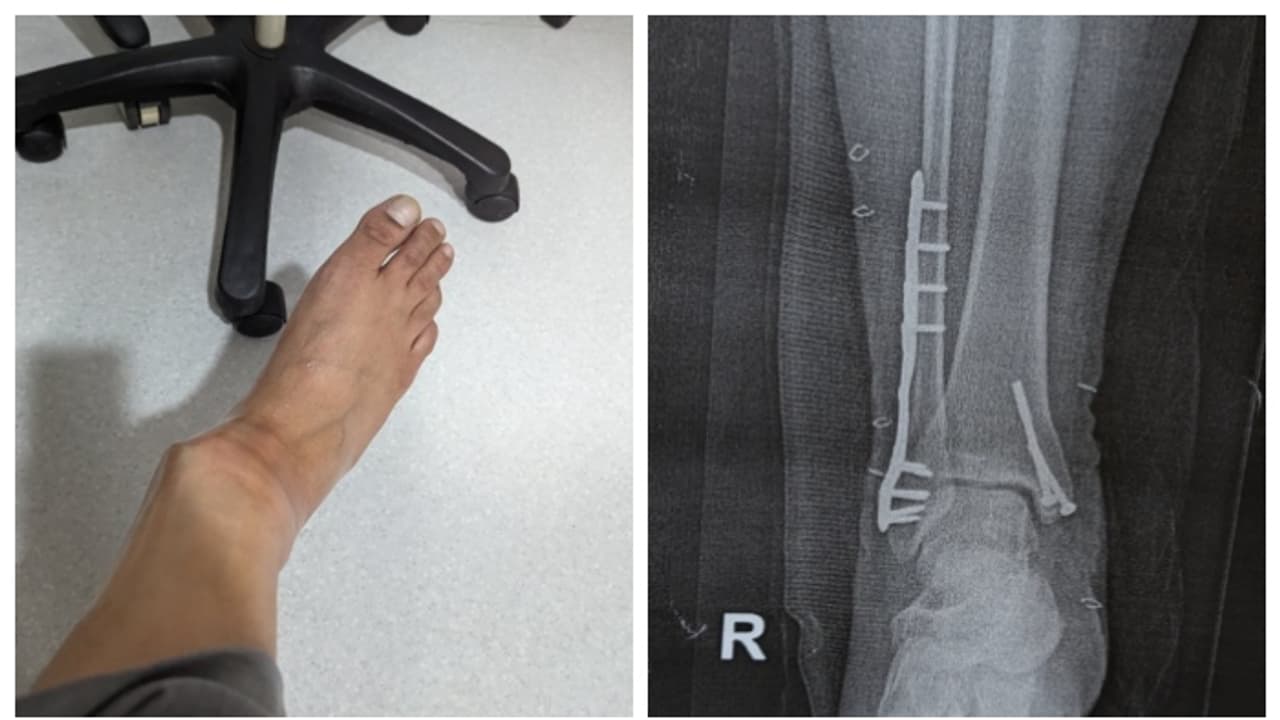

"ഓഗസ്റ്റ് 14 ന് പുലർച്ചെ ചെന്നൈയിൽ നിന്നുള്ള ഇൻഡിഗോ വിമാനത്തിൽ ഞാൻ ദില്ലിയിലെ ടി 2 ൽ എത്തി. അവരിൽ ഏറ്റവും സാധാരണമായതുപോലെ, എയറോബ്രിഡ്ജ് നൽകിയിട്ടില്ല, പകരം എല്ലാവരോടും അവരുടെ റാമ്പുകൾ ഉപയോഗിച്ച് ഇറങ്ങാൻ ആവശ്യപ്പെട്ടു," അദ്ദേഹം എഴുതി. മഴയുണ്ടായിരുന്നതിനാല് യാത്രക്കാര്ക്ക് ഉപയോഗിക്കാന് നല്കിയ റാമ്പ് നനഞ്ഞിരുന്നു. ഈർപ്പം കാരണം പാതിവഴിയെത്തിയപ്പോള് തന്റെ വലതു കാൽ റാമ്പിലെ ഈർപ്പമുള്ള ഭാഗത്തേക്ക് വഴുതി. പിന്നാലെ താഴെ വീണു. ഒന്നെങ്കില് കണങ്കാല് ഒടിയുകയോ സ്ഥാനം മാറുകയോ ചെയ്തതായി അപ്പോള് തന്നെ തനിക്ക് തോന്നിയതായും അദ്ദേഹം കുറിച്ചു. സഹയാത്രികരുടെ സഹായത്തോടെയാണ് താന് അവിടെ നിന്നും എഴുന്നേറ്റത്. ആ അപകടത്തിന് ശേഷമുള്ള വളഞ്ഞിരിക്കുന്ന കാലിന്റെ പടം പങ്കുവച്ച് കൊണ്ട് രത്നേന്ദു റേ എഴുതി.

ഇൻഡിഗോ ജീവനക്കാർ വീൽചെയറിൽ കിടത്തി ടെർമിനലിലെ ക്ലിനിക്കിലേക്ക് കൊണ്ടുപോയി. പരിശോധനയില് കണങ്കാല് തകർന്നതായി കണ്ടെത്തി. എയർസേവ പോർട്ടലിൽ പരാതി രജിസ്റ്റർ ചെയ്തെങ്കിലും മറ്റാരും വഴുതി വീണിട്ടില്ലാത്തതിനാല് റാമ്പ് നനഞ്ഞിരുന്നില്ലെന്നും താന് തന്നെ വഴുതി വീണതാണെന്നുമായിരുന്നു ഇൻഡിഗോയുടെ പ്രതികരണം. ഇത് തനിക്ക് അപമാനമായി തോന്നിയെന്നു അദ്ദേഹം കുറിച്ചു. തനിക്ക് ശരിക്കും നടക്കണമെങ്കില് ഇനി കുറഞ്ഞത് ഒരു വര്ഷമെങ്കിലും എടുക്കും. വലത് കണങ്കാലിൽ ഒരു പ്ലേറ്റും സ്ക്രൂകളുമുണ്ട്, ചെറിയ ചലന ശേഷി മാത്രം. രണ്ട് ശസ്ത്രക്രിയകളുടെ പാടുകൾ, ഫിസിയോതെറാപ്പിക്കും ദിനചര്യയ്ക്കുമായി ഇപ്പോള് ഒരു വാക്കറിനെ ആശ്രയിക്കുകയാണെന്നു അദ്ദേഹം എഴുതി.